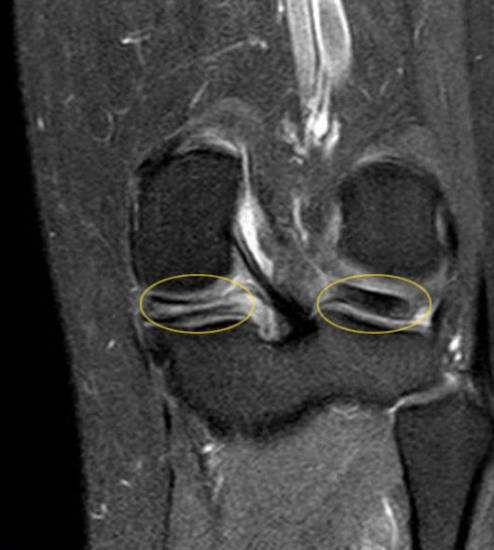

Травма колена визуализирует четкий горизонтальный разрыв мениска вдоль его продольной оси (желтая маркировка слева). Другой мениск коленного сустава (справа) не поврежден, что доказывает более объемная затемненная область. joint-surgeon

Перед операцией врач проводит комплексное клиническое обследование. Как правило опытный специалист по лечению заболеваний колена сможет диагностировать разрыв во время составления анамнеза и физического осмотра пацинета. Во время клинического осмотра врач проверяет подвижность коленного сустава в разных положениях, оценивает походку, а также тестирует как сгибается и разгибаетеся нога. Особенно в области суставной щели разрыв мениска вызавает четкую боль, что является довольно точным подтверждением диагноза с клинической точки зрения.

В отличие от рентгена, на котором в основном визуализируются кости, МРТ (магнитно-резонансная томография) предоставляет точные снимки всех структур мягких тканей. Таким образом, Ваш лечащий врач сможет оценить состояние сухожилий, связок и хрящевидных менисков. Возможность получения детальных изображений разрыва мениска делает данное облседование особенно значимым. При помощи МРТ можно увидеть точное положение разрыва, а так же установить его его длину и ход.